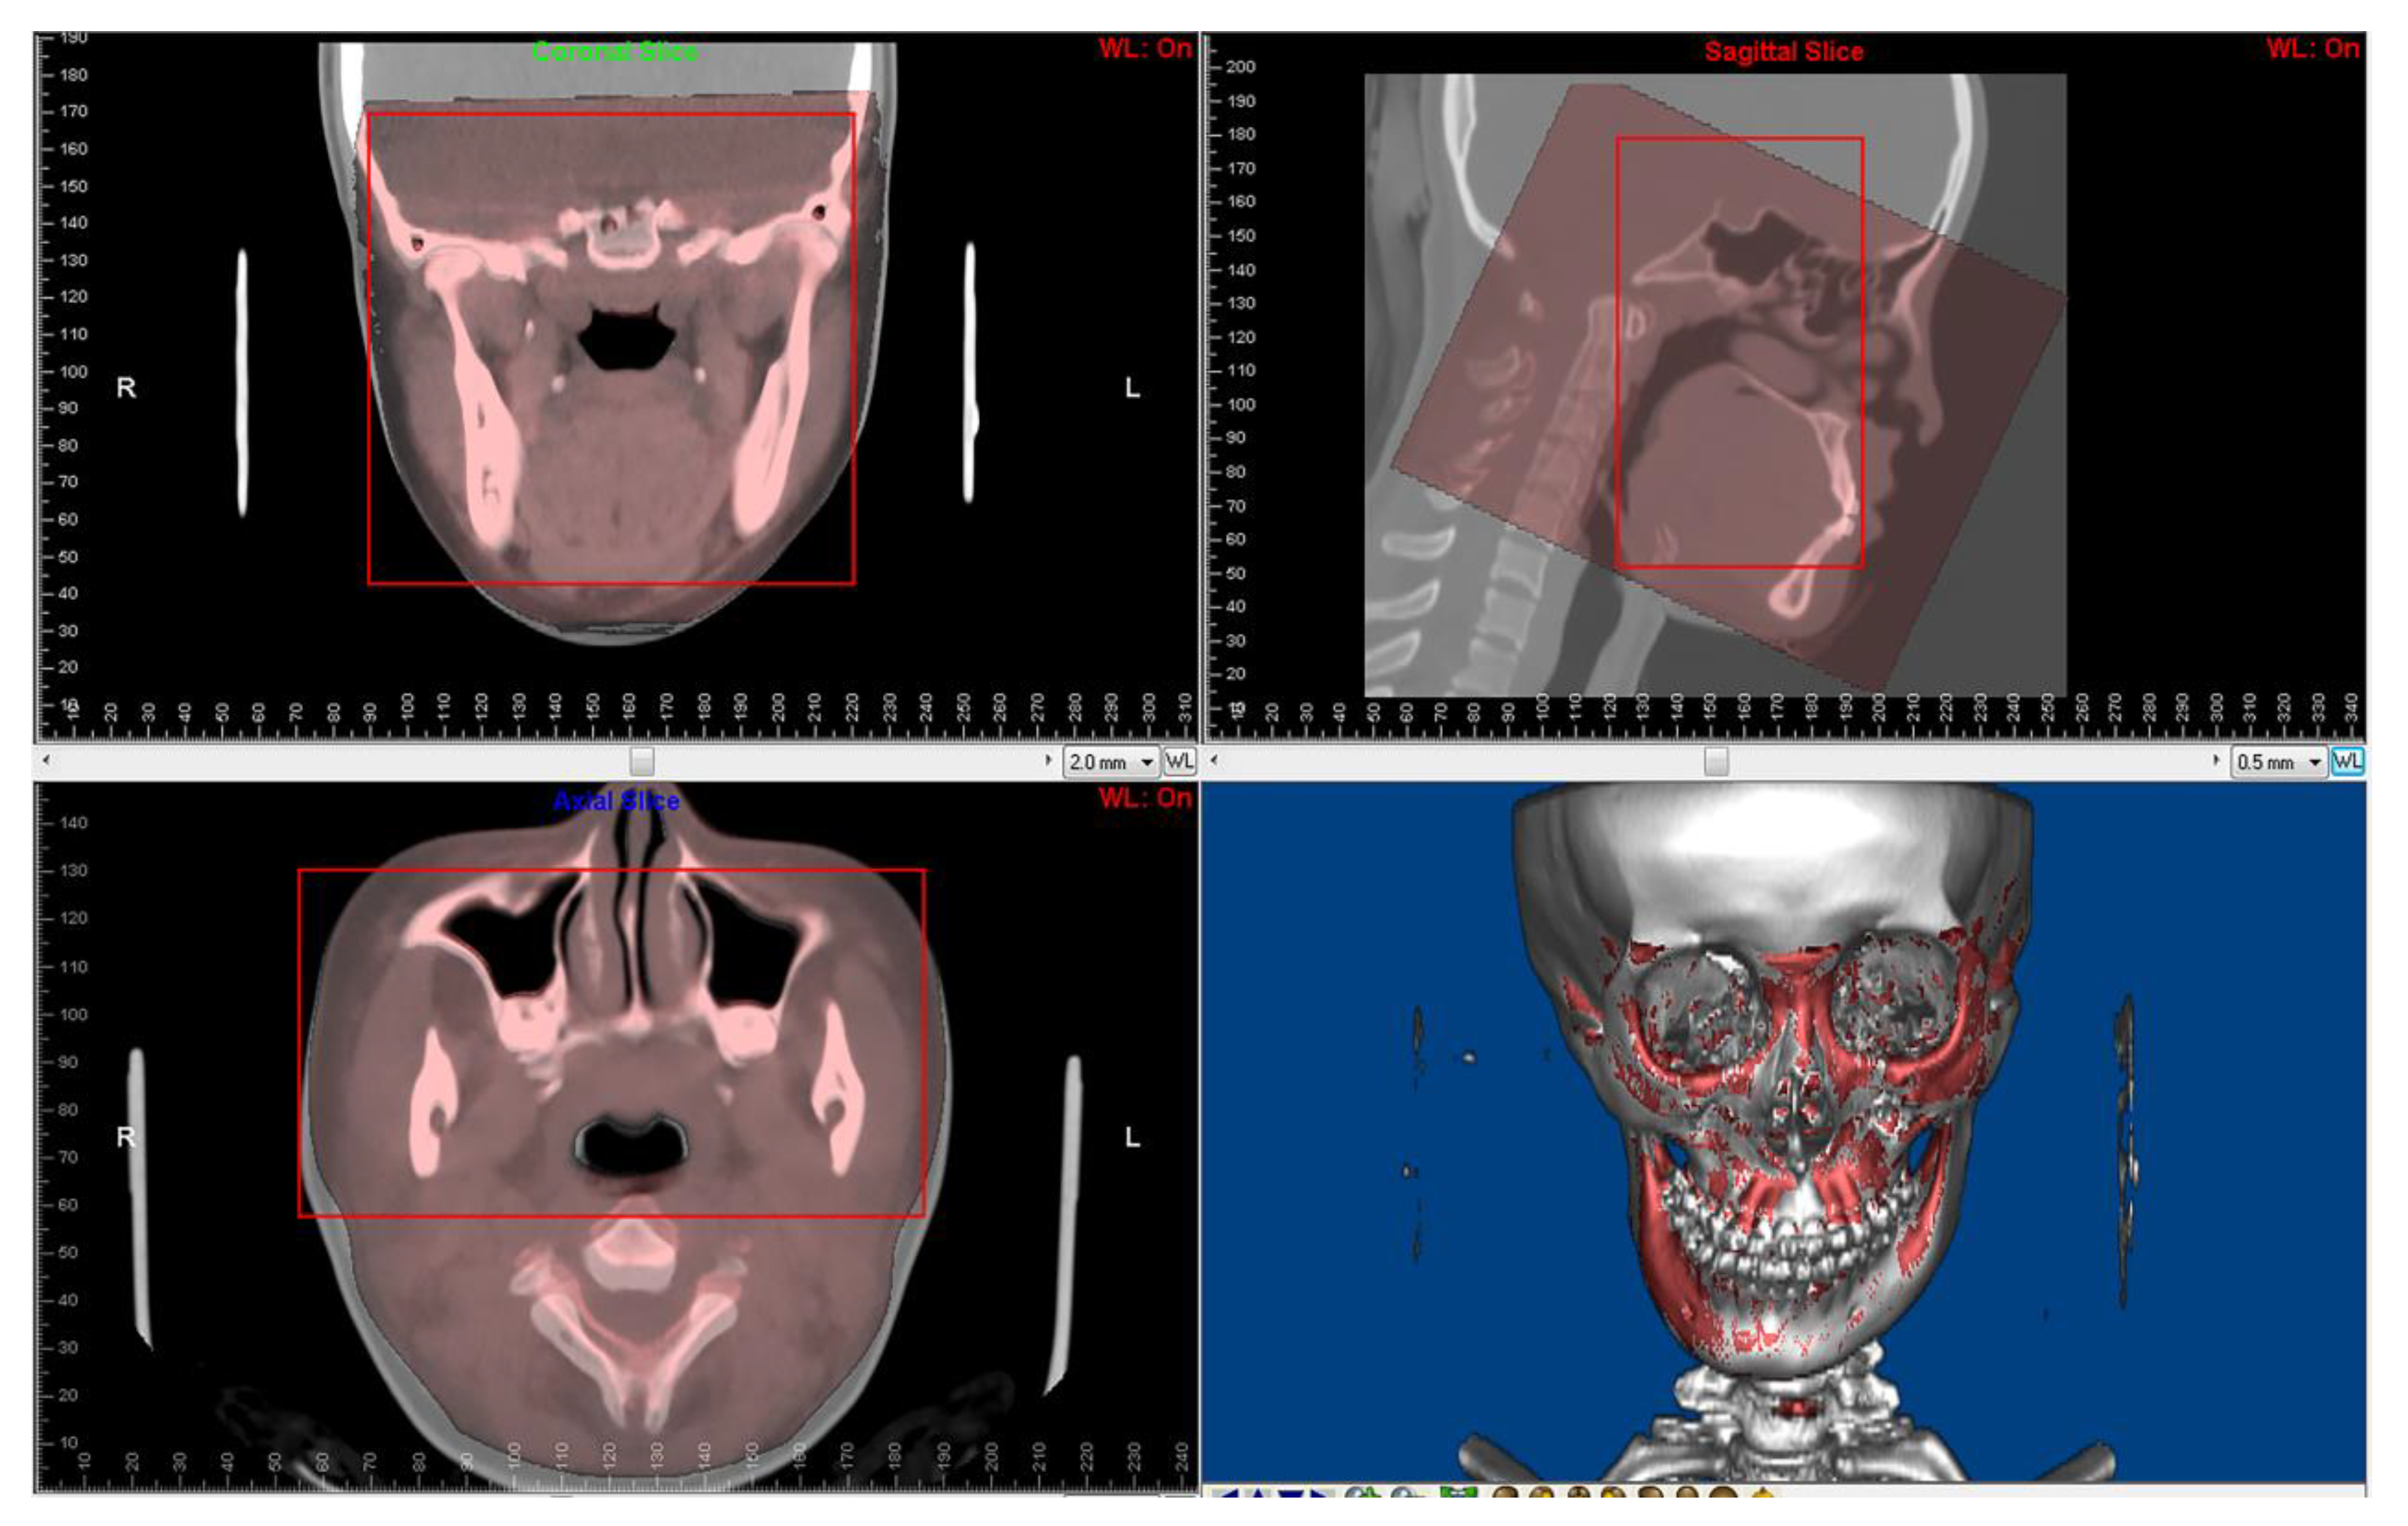

2.3. CBCT to CT Superimposition

Figure 2.

Superimposition of paired CT and CBCT was performed using Dolphin3D imaging software. The red squares are regions for superimposition.